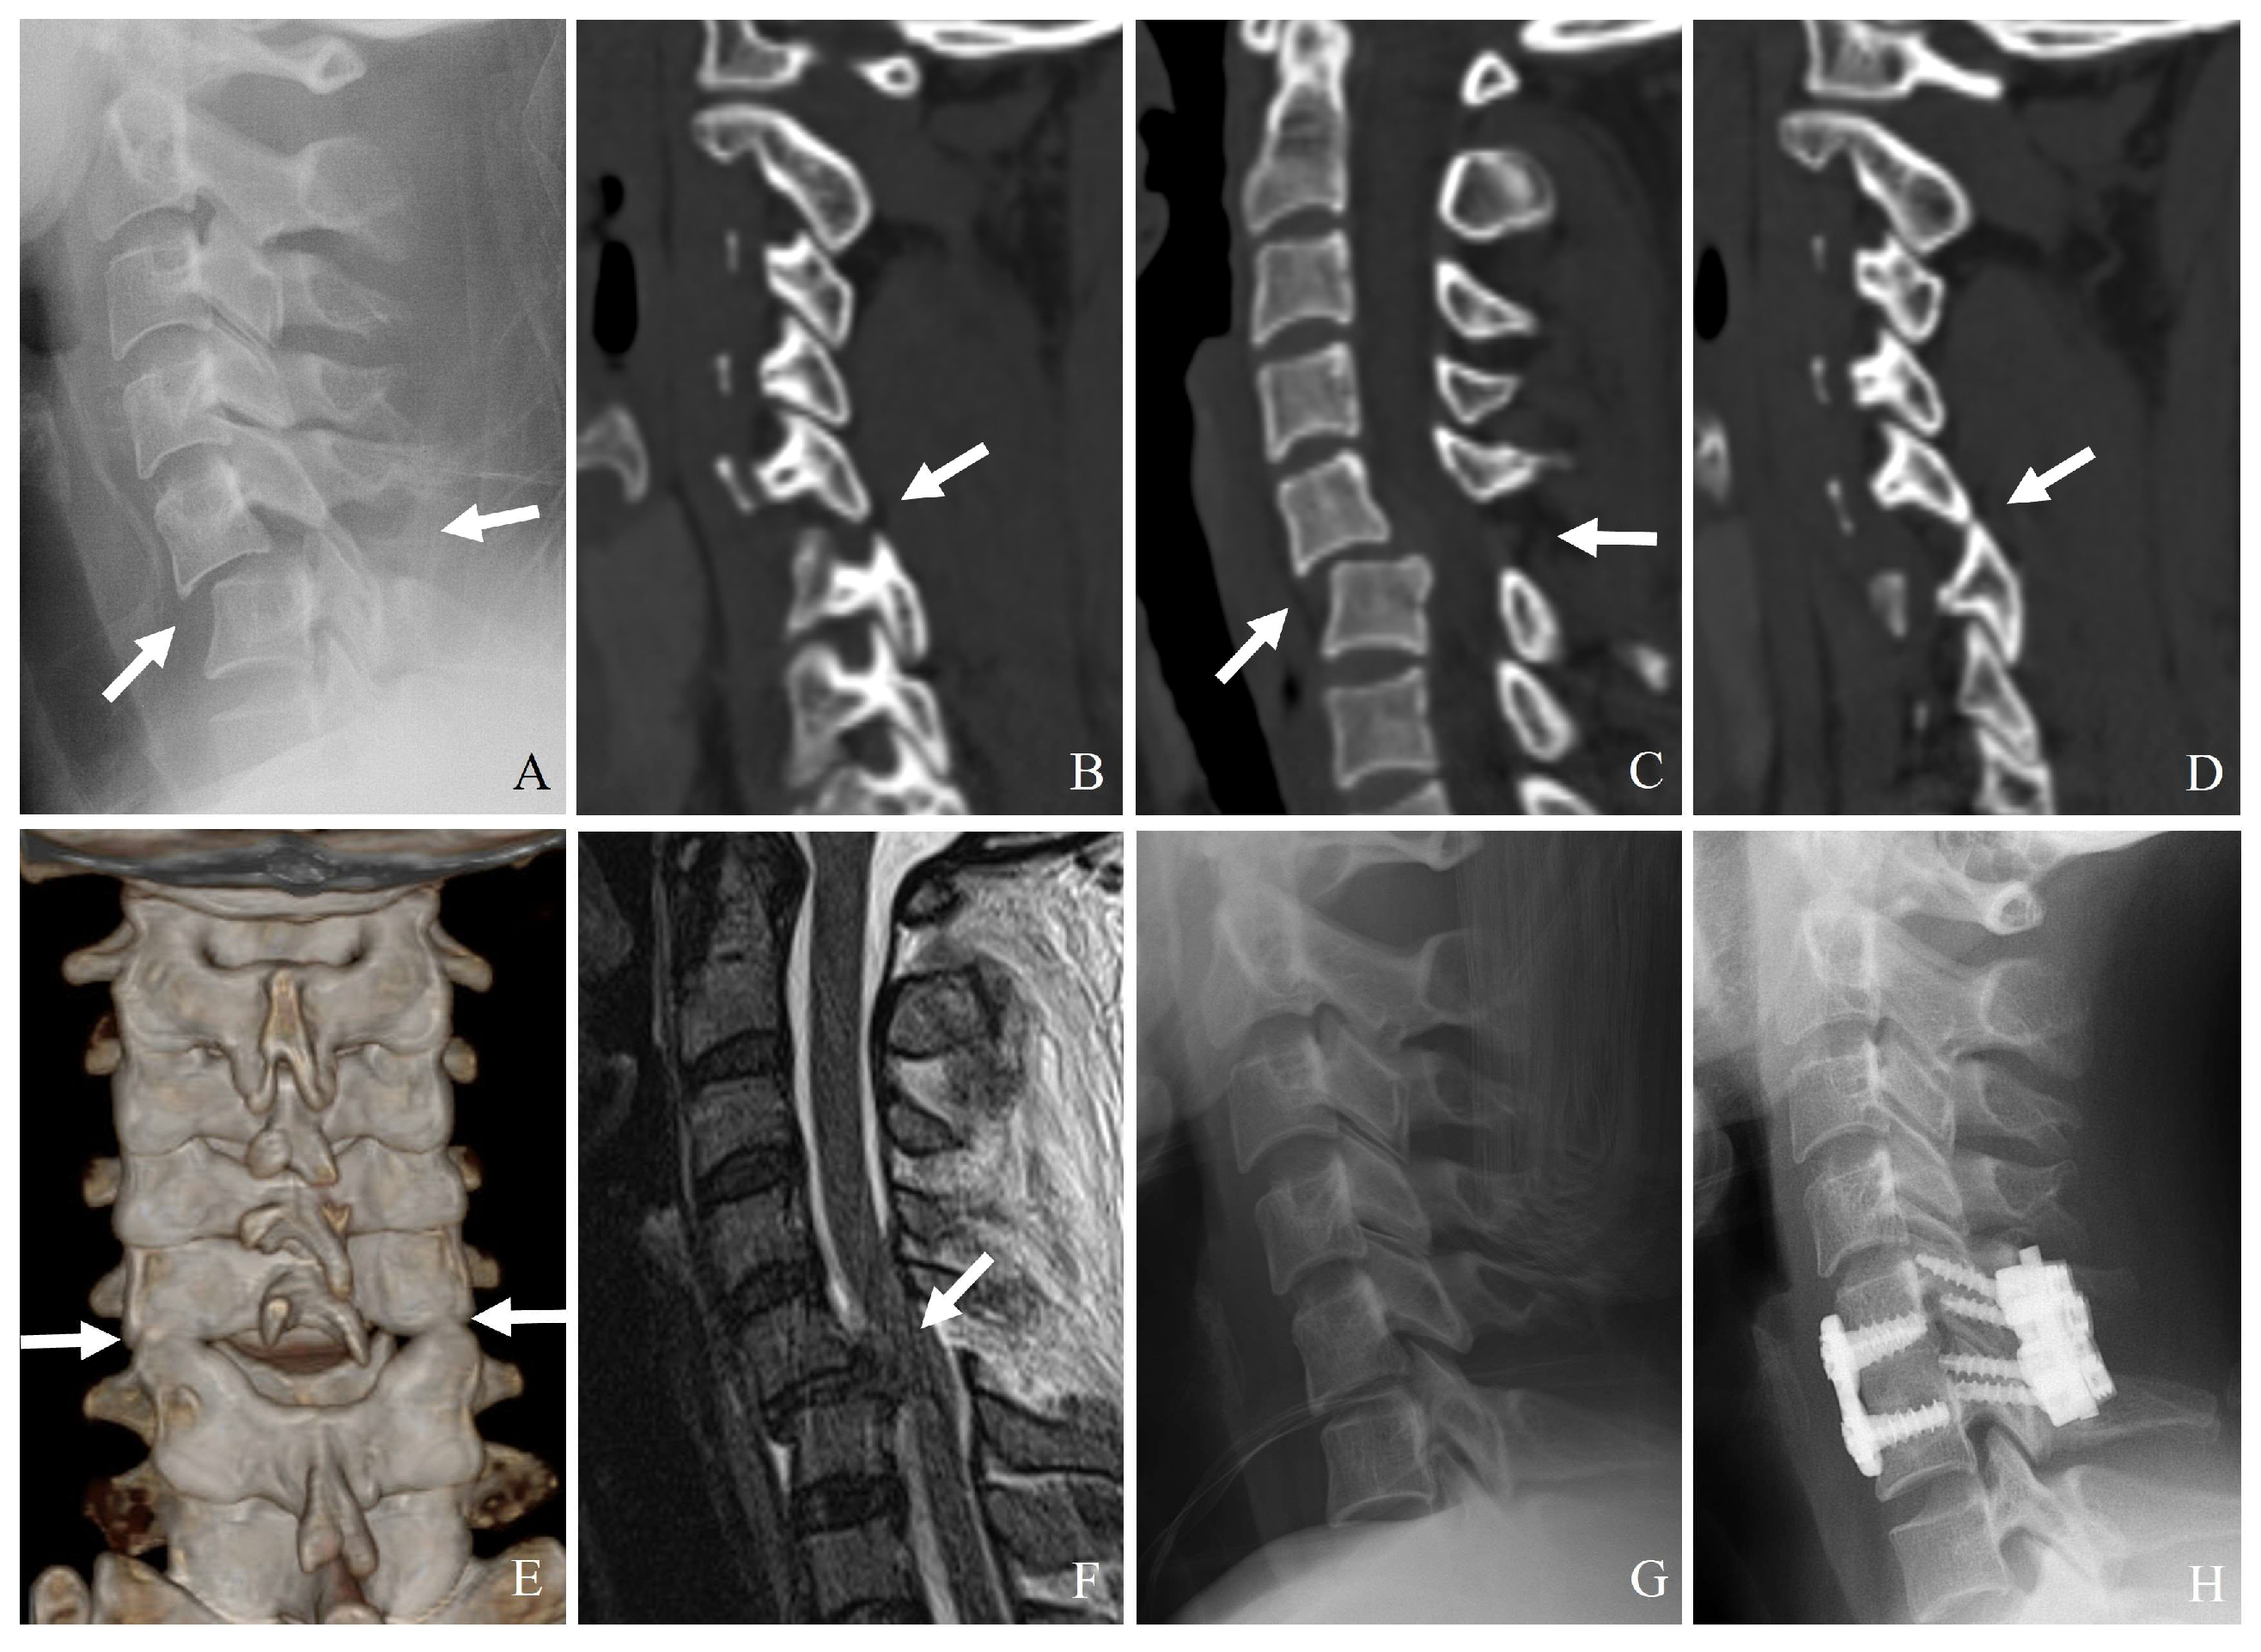

3.1. Plain Radiography

3.2. Computed Tomography (CT)

- (1)

- Identifying minimally displaced facet fractures that may be missed on radiographs.

- (2)

- Assessing lateral mass comminution and fracture propagation.

- (3)

- Evaluating facet joint alignment in axial and sagittal reconstructions.

- (4)

- Determining the extent of impaction or subluxation.

| F1 Fracture | Nondisplaced or minimally displaced facet fracture | CT: Hairline or incomplete fracture without subluxation or misalignment. MRI: Minimal or no disruption of the DLC. | Mechanically stable; treated conservatively with immobilization. |

| F2 Fracture | Displaced facet fracture without significant instability | CT: Displaced fracture, but no complete subluxation or dislocation. Fracture extends < 40% into vertebral body. MRI: Partial PLC injury, intact DLC. | May be treated conservatively; surgical stabilization if symptoms progress. |

| F3 Fracture | Unstable facet fracture with significant displacement or dislocation | CT: Completely displaced or perched facet with significant translation and rotation. Fracture extends ≥ 40% into vertebral body. MRI: Complete disruption of PLC and DLC. | Highly unstable; surgical intervention usually required to prevent neurological deterioration. |

| F4 Fracture | Comminuted facet fracture with severe instability | CT: Highly comminuted fragment with vertebral displacement. MRI: Complete ligamentous disruption and extensive soft tissue injury. | Requires immediate surgical intervention; posterior fusion or combined stabilization. |